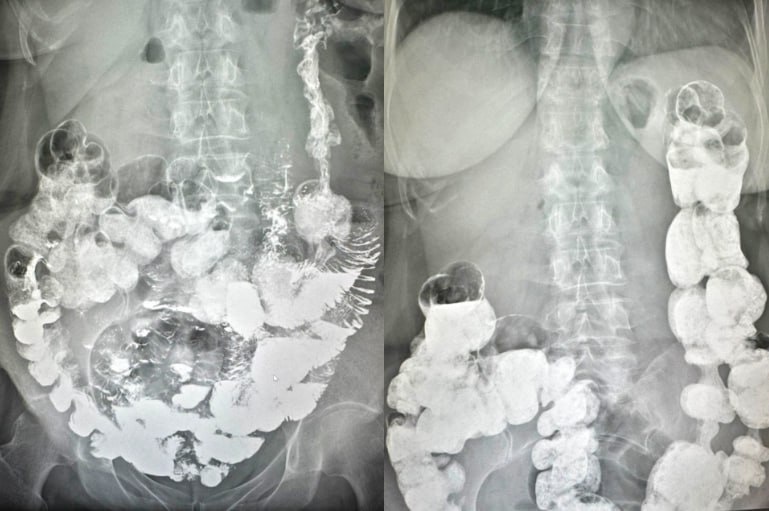

ΠŸΡ€ΠΈ ΠΏΠ΅Ρ€Π²ΠΈΡ‡Π½ΠΎΠΌ осмотрС гастроэнтСролог Абидат АтаСва Ρ‚Ρ‰Π°Ρ‚Π΅Π»ΡŒΠ½ΠΎ собрала Π°Π½Π°ΠΌΠ½Π΅Π· ΠΈ ΠΈΠ·ΡƒΡ‡ΠΈΠ»Π° ΠΏΡ€Π΅Π΄ΠΎΡΡ‚Π°Π²Π»Π΅Π½Π½ΡƒΡŽ ΠΌΠ΅Π΄ΠΈΡ†ΠΈΠ½ΡΠΊΡƒΡŽ Π΄ΠΎΠΊΡƒΠΌΠ΅Π½Ρ‚Π°Ρ†ΠΈΡŽ. Для уточнСния Π΄ΠΈΠ°Π³Π½ΠΎΠ·Π° ΠΈ опрСдСлСния дальнСйшСй Ρ‚Π°ΠΊΡ‚ΠΈΠΊΠΈ лСчСния Π²Ρ€Π°Ρ‡ Ρ€Π΅ΠΊΠΎΠΌΠ΅Π½Π΄ΠΎΠ²Π°Π»Π° Π΄ΠΎΠΏΠΎΠ»Π½ΠΈΡ‚Π΅Π»ΡŒΠ½ΠΎΠ΅ обслСдованиС, ΠΊΠΎΡ‚ΠΎΡ€ΠΎΠ΅ Ρ€Π°Π½Π΅Π΅ ΠΏΠ°Ρ†ΠΈΠ΅Π½Ρ‚ΠΊΠ΅ Π½Π΅ ΠΏΡ€ΠΎΠ²ΠΎΠ΄ΠΈΠ»ΠΈ - рСнтгСнологичСскоС исслСдованиС с пассаТСм бария.

По Π΅Π³ΠΎ Ρ€Π΅Π·ΡƒΠ»ΡŒΡ‚Π°Ρ‚Π°ΠΌ выявлСны ΠΏΡ€ΠΈΠ·Π½Π°ΠΊΠΈ синдрома ΠŸΠ°ΠΉΡ€Π° (высокая фиксация сСлСзСночного ΠΈΠ·Π³ΠΈΠ±Π°) ΠΈ трансвСрзоптоз. На основании ΠΆΠ°Π»ΠΎΠ±, Π°Π½Π°ΠΌΠ½Π΅Π·Π° ΠΈ ΠΏΠΎΠ»ΡƒΡ‡Π΅Π½Π½Ρ‹Ρ… Π΄Π°Π½Π½Ρ‹Ρ… ΠΏΡ€ΠΈ обслСдовании Π±Ρ‹Π» установлСн Π΄ΠΈΠ°Π³Π½ΠΎΠ·: болСзнь ΠŸΠ°ΠΉΡ€Π°.